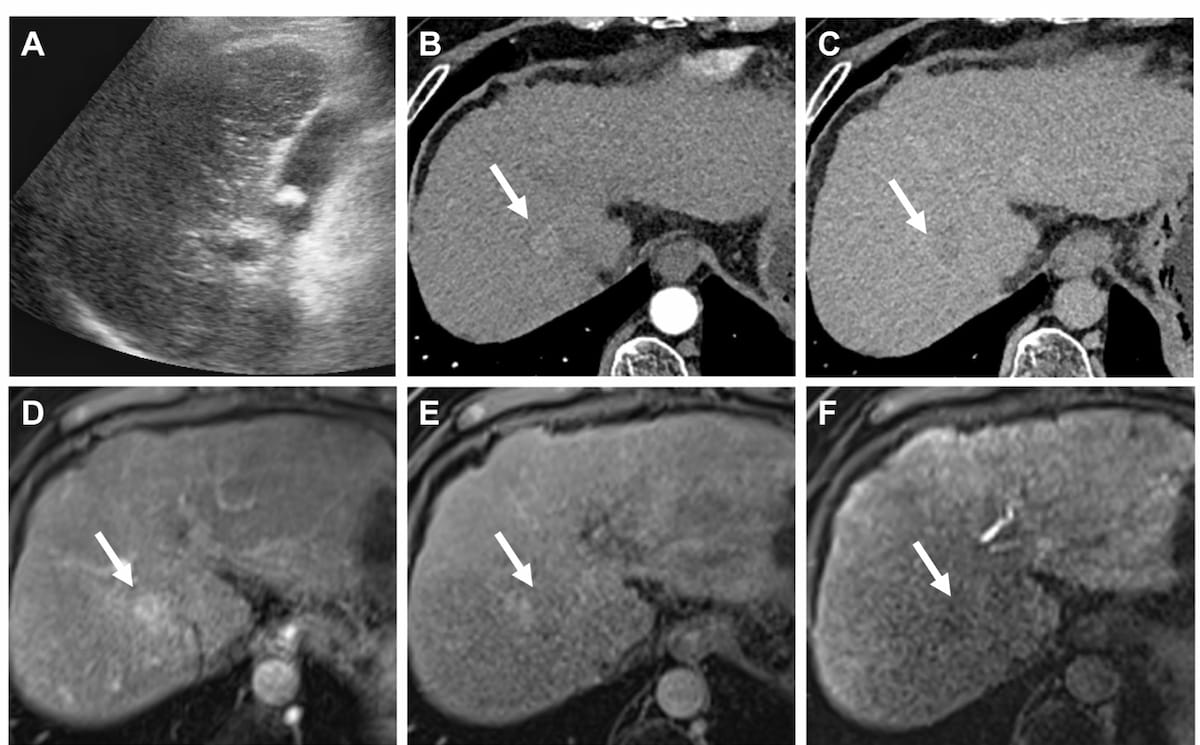

Ultrasound-derived fat fraction assessment offered higher AUCs for differentiating mild, moderate and severe hepatic steatosis in comparison to established noninvasive measures of metabolic dysfunction-associated steatosis liver disease (MASLD), according to new multicenter research.

Reportedly the only point-of-care ultrasound system that can estimate liver stiffness and attenuation that correlate to MRI-PDFF, Velacur One also may facilitate higher reimbursement than non-imaging elastography.